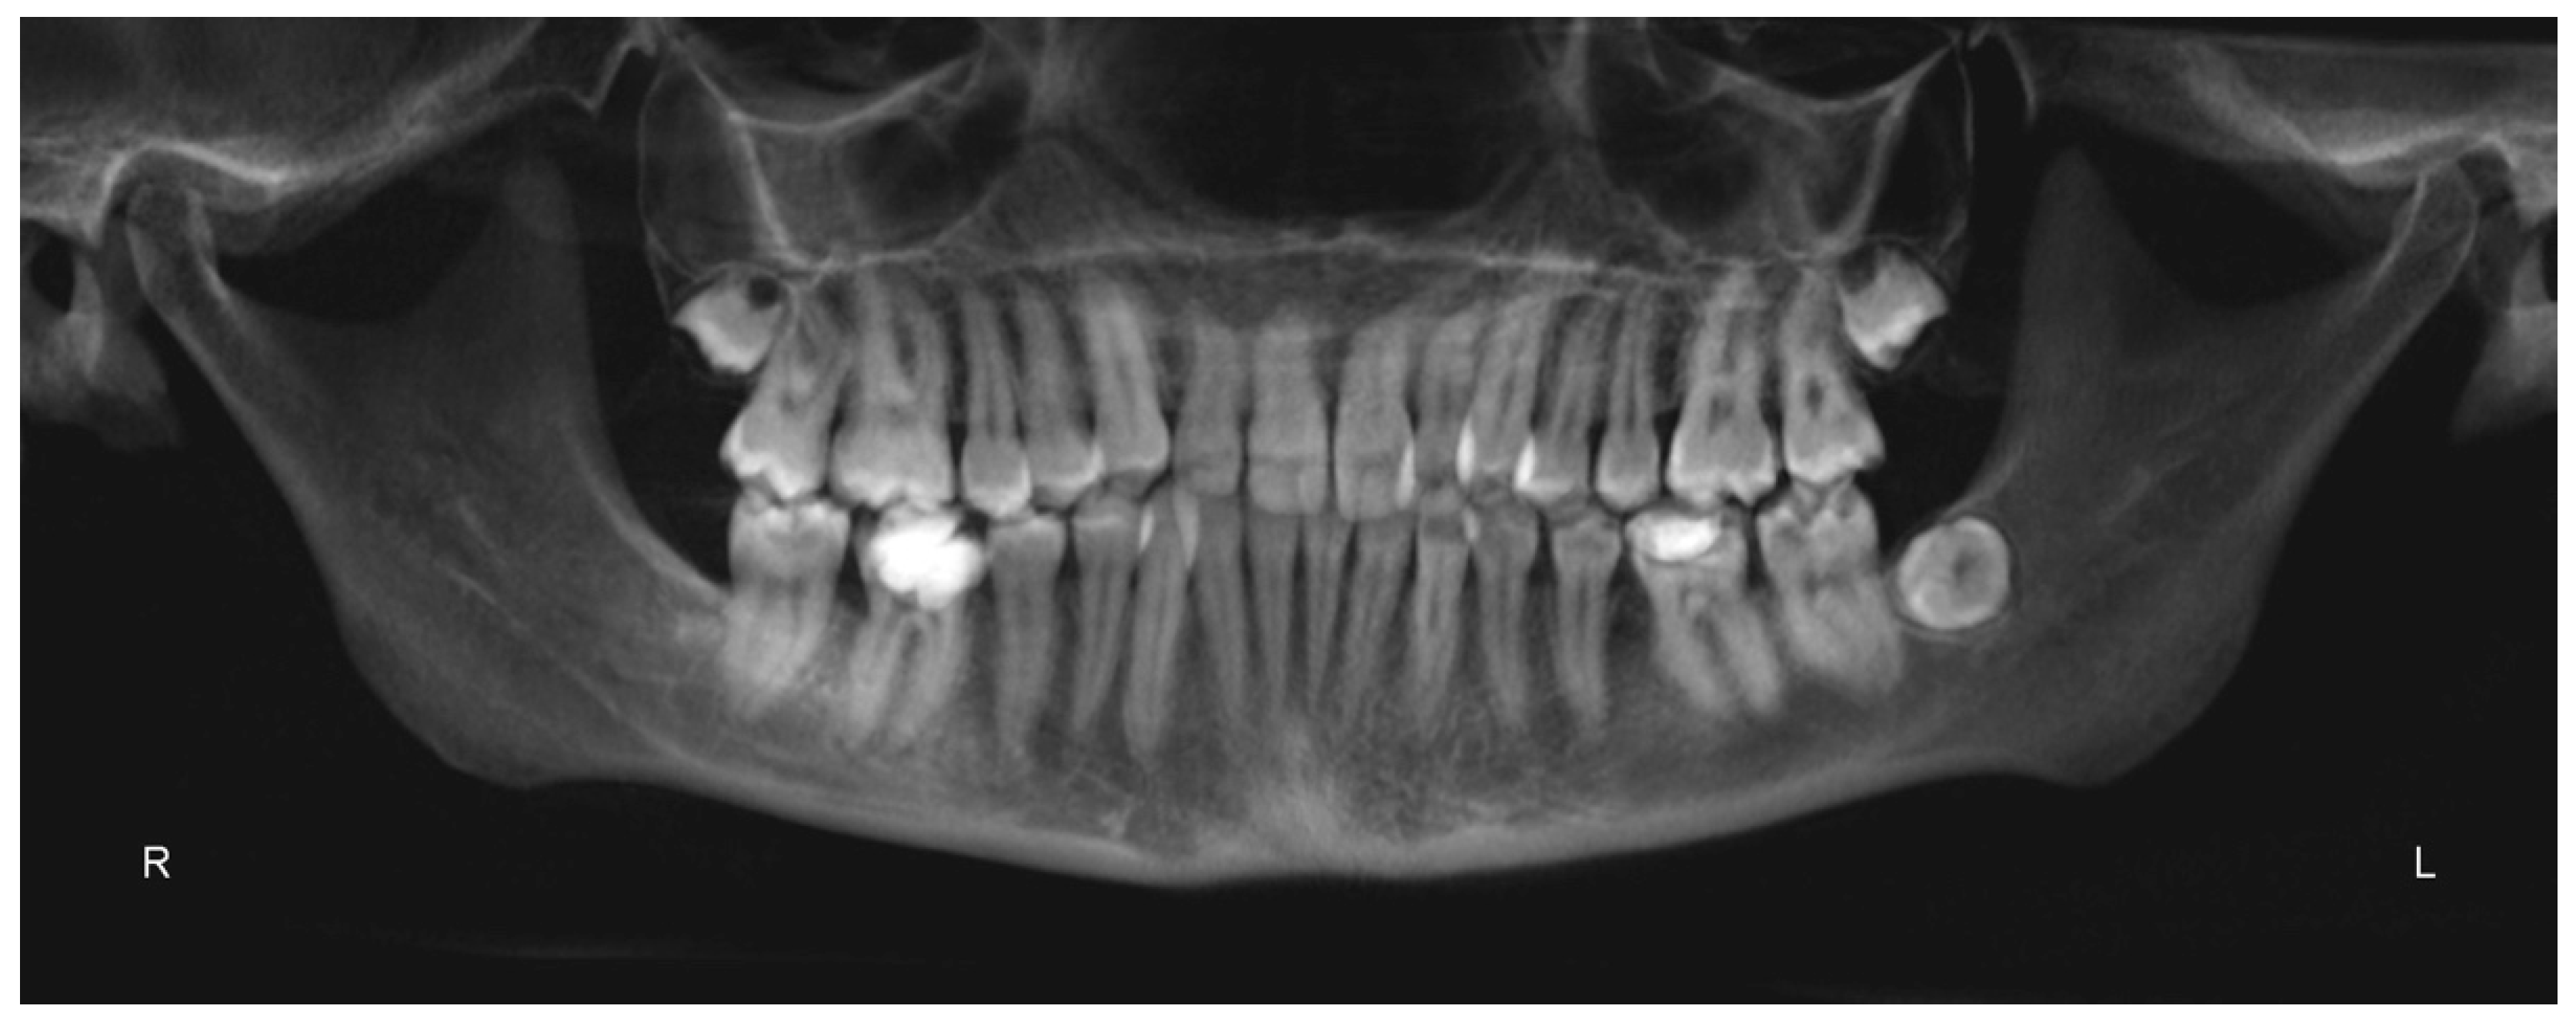

Figure 9.

Panorex.